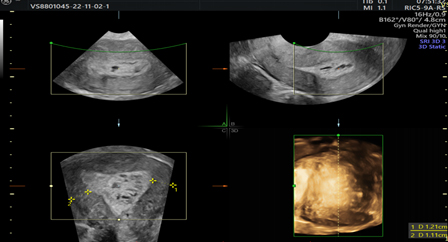

Picture 3. 2D and 3D ultrasonographic images with heterogeneous endometrium.

Picture 4. Doppler view of heterogeneous endometrium with interrupted endometrial myometrial junction and scattered blood vessels.

Picture 5.Prominent Doppler flow diagram.

Picture 6.Showing tumor invasion into the cervical stroma, visualizes clear demarcation of tumor echogenicity from the cervical stroma.

Regarding 3D Ultrasonography, there are different data regarding its effectiveness in predicting deep myometrial and cervical stromal invasion. Its advantages are that it can provide significant information about myometrial invasion of the uterine angles in a coronary section (23).

The possibilities of 3D ultrasonography, such as volume computerized imaging, computerizedultrasonographic tomography and rendering, can help assess myometrial and cervical invasion (Picture 3) (24).